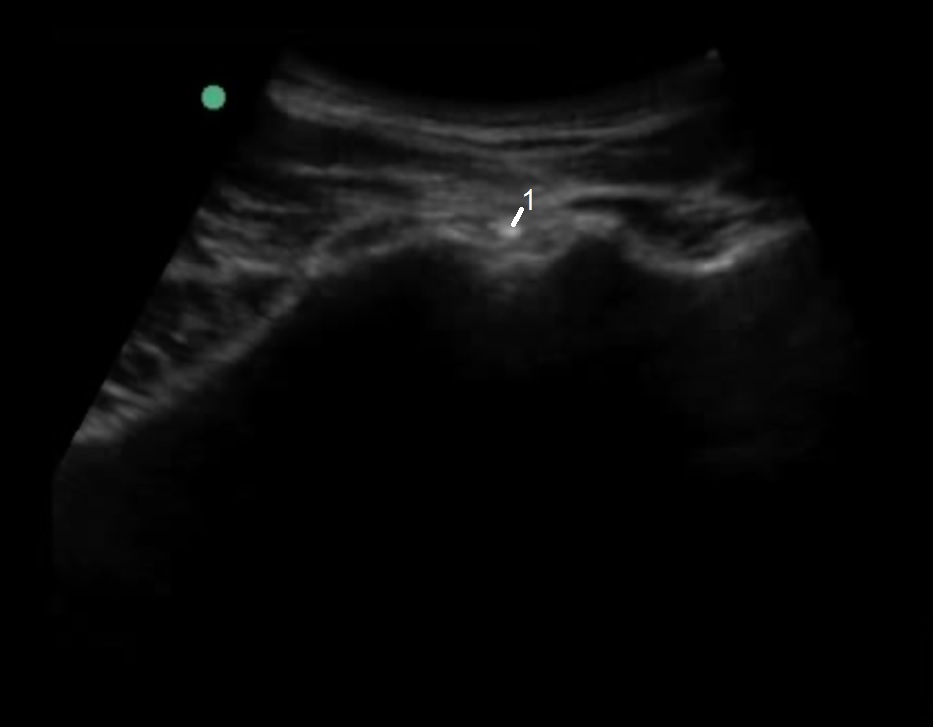

腰仙腸関節針の先端の画像

針の先端